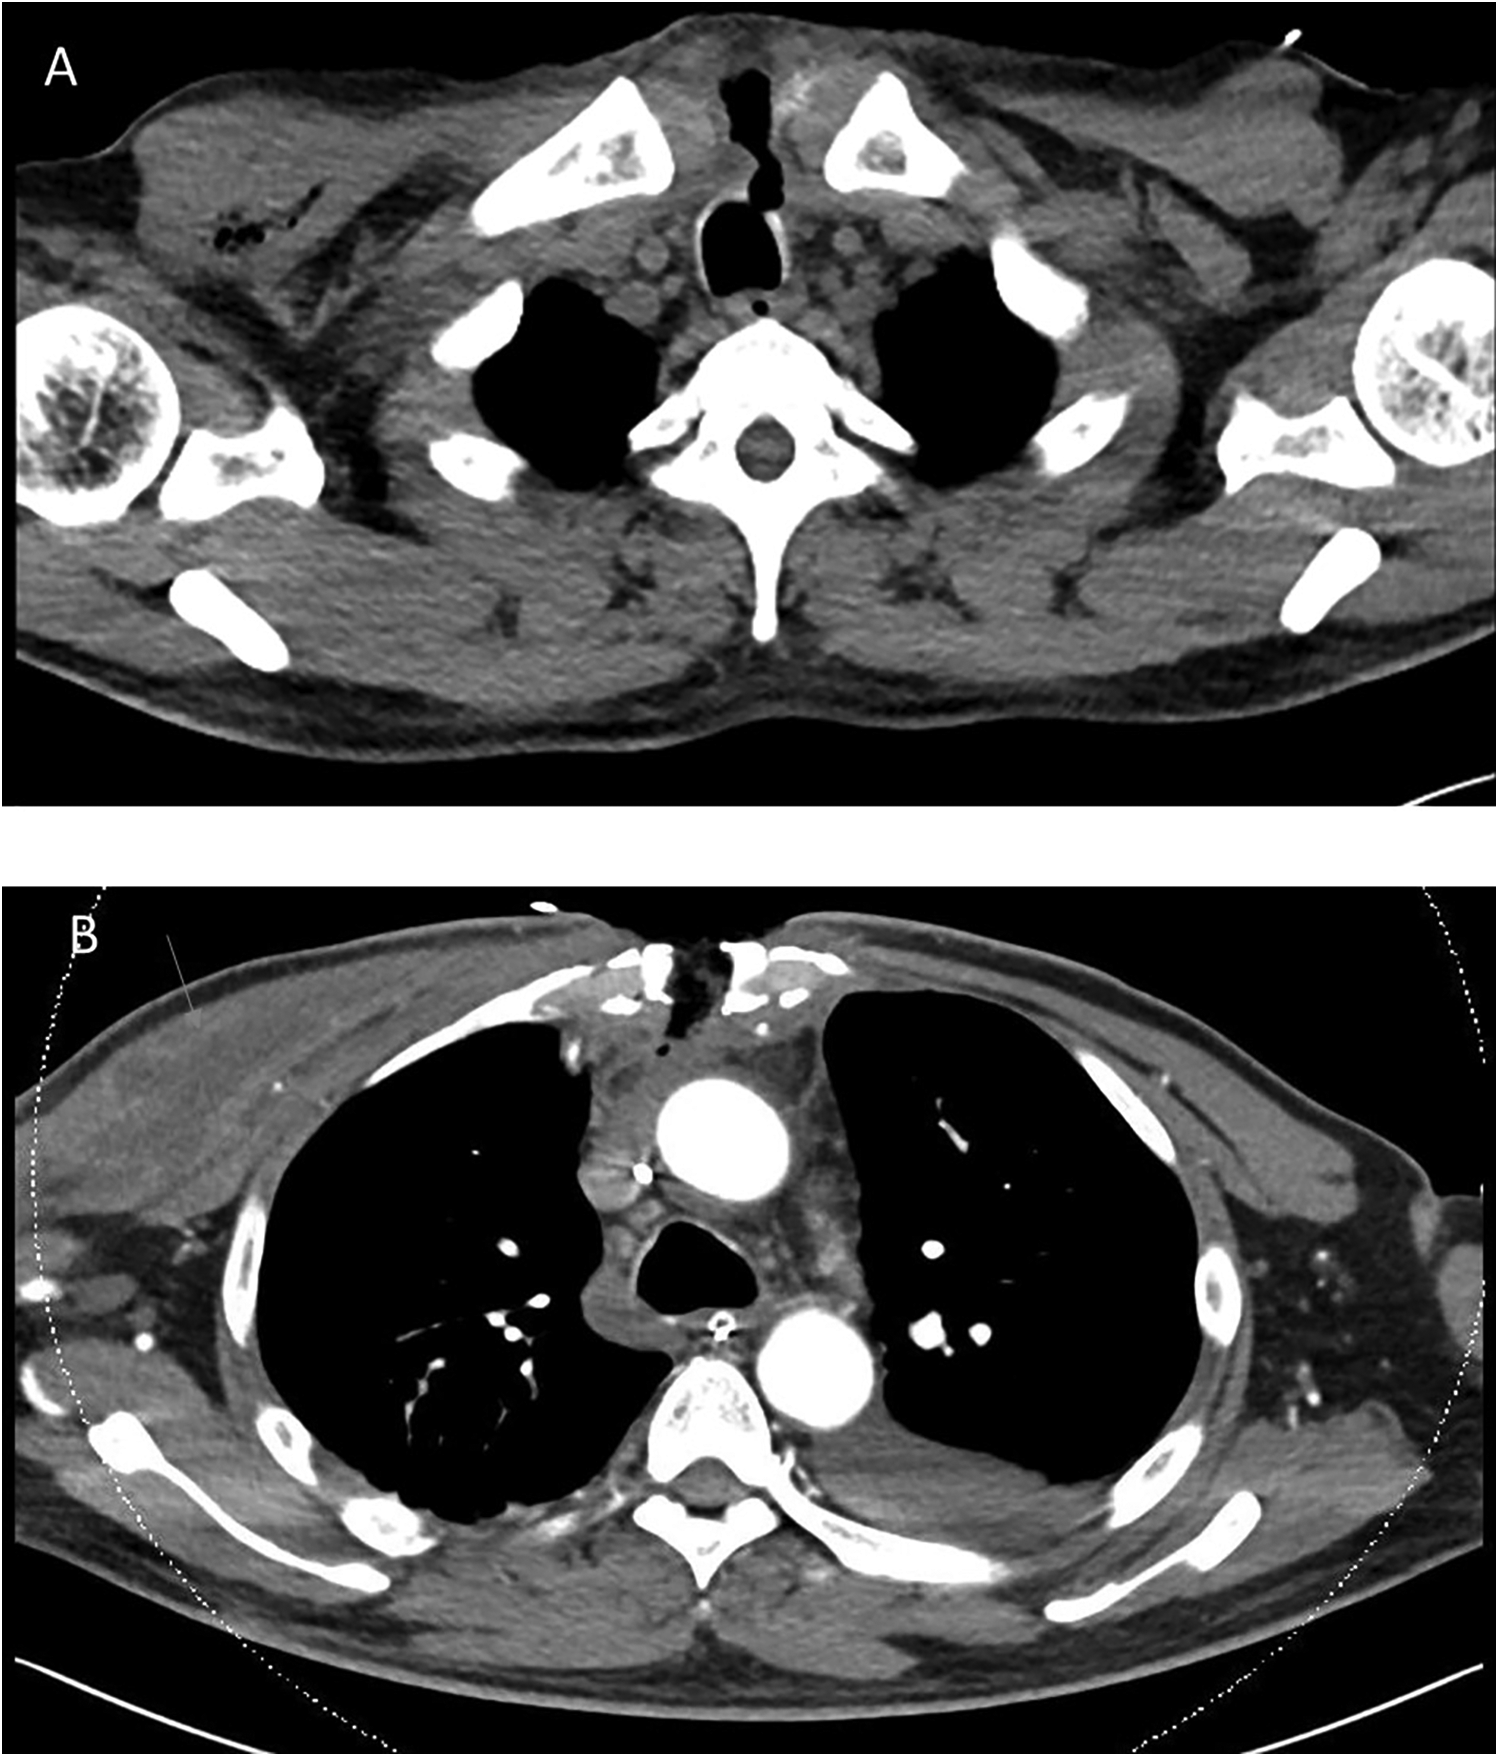

The patient was readmitted 2 days later with complaints of worsening cough, blood-tinged sputum, orthopnea, pedal edema, fatigue, and purulent discharge from the upper part of his sternal wound. He was afebrile, with a blood pressure of 84/59 mmHg and a heart rate of 70 beats per minute. Physical examination revealed a small (3 mm) wound over his midline sternotomy that moved with respiration. His heart sounds were normal, but pulmonary crepitations were noted. A bedside echocardiogram showed a moderate-sized pericardial effusion (1.6 cm) without any features of tamponade. Blood test results were as follows: Hb 10.4 g/dL, WBC 14.5 × 109/L, platelet count 99 × 109/L, CRP 313 mg/L, procalcitonin 2.6 µg/L, and creatinine 314 µmol/L. An urgent chest CT showed a tracheal fistula to the subcutaneous sternum along the sternotomy defect and subcutaneous emphysema along the manubrium sternum, posterior sternum, and mediastinum, extending over the right chest wall. A small pericardial effusion and mid- and lower-sternal wire dehiscence were noted. The CT features were suggestive of mediastinitis, no large mediastinal collections were seen (Figure 2).

Figure 2

Patient's chest CT. (A) chest CT performed during his second readmission showing a tracheocutaneous fistula from the upper trachea to the subcutaneous sternum along the sternotomy defect. There was subcutaneous emphysema along the manubrium sternum, posterior sternum, and mediastinum, extending over the right chest wall. No large mediastinal collection was noted in the study. (B) Follow-up chest CT performed 1 week later showing interval development of a pectoralis major abscess (arrow), which required further surgical drainage.

The patient was stabilized and underwent sternal reopening, mediastinal washout, and application of a vacuum-assisted closure (VAC) dressing. Intraoperatively, the lower four sternal wires were noted to be fractured, and unhealthy tissue with areas of fat necrosis was noted over the sternum. However, no frank pus or mediastinal abscess was observed. The following day, a relook surgery was performed, and a temporary seal of the tracheal defect was achieved with a Hemopatch. An interval chest CT at 1 week showed the development of an abscess in the right pectoralis major muscle. He underwent further surgery with an exploration of the neck, repair of the tracheal defect with a sternocleidomastoid muscle flap, debridement of the chest wound, and drainage of the right pectoralis major abscess. He eventually underwent sternal plating and primary closure of the right chest wall wound on post-operative day 9 from the sternal reopening surgery. Wound and sternal bone cultures grew Klebsiella and Streptococcus anginosus, while blood cultures grew S. anginosus. The patient was initially treated with intravenous meropenem and vancomycin before eventually switching to ceftriaxone and metronidazole. He was eventually discharged on post-operative day 17 with oral levofloxacin and metronidazole for an additional 4 weeks. One week after discharge, he was reviewed in the clinic and was noted to have a small area of skin erythema and bogginess (1.5 cm) over the upper part of his chest wound. He was readmitted for sternal wound debridement to the level of the sternal plate, followed by VAC dressing application until wound coverage was achieved 2 weeks later. He remained well during subsequent follow-up visits, and there were no further issues with wound healing or cardiac symptoms (Figure 3).

Tracheomediastinal fistulas are rare and more often seen in patients with cancer (7, 8) or following chemoradiation therapy (9). They have also been described after transbronchial biopsies (10). Routine airway intubation and ventilation have not been shown to cause tracheomediastinal fistulas. The tracheal fistula in our patient was likely from mediastinitis, with tracking of the infection to the trachea and the skin. Although no frank mediastinal abscess was noted on CT scan or intraoperatively, it is possible that an early mediastinal abscess could have drained via the fistula, both into the trachea (accounting for his cough) and subcutaneously to the skin. The infection likely also tracked subcutaneously to the right pectoralis major, where it later formed an abscess collection. In our patient, the most likely cause of his mediastinitis is a post-operative deep sternal wound infection; a less likely differential is bacterial seeding from the pericardiocentesis procedure. The deep sternal wound infection likely caused the mediastinitis and the reactive pericardial effusion.